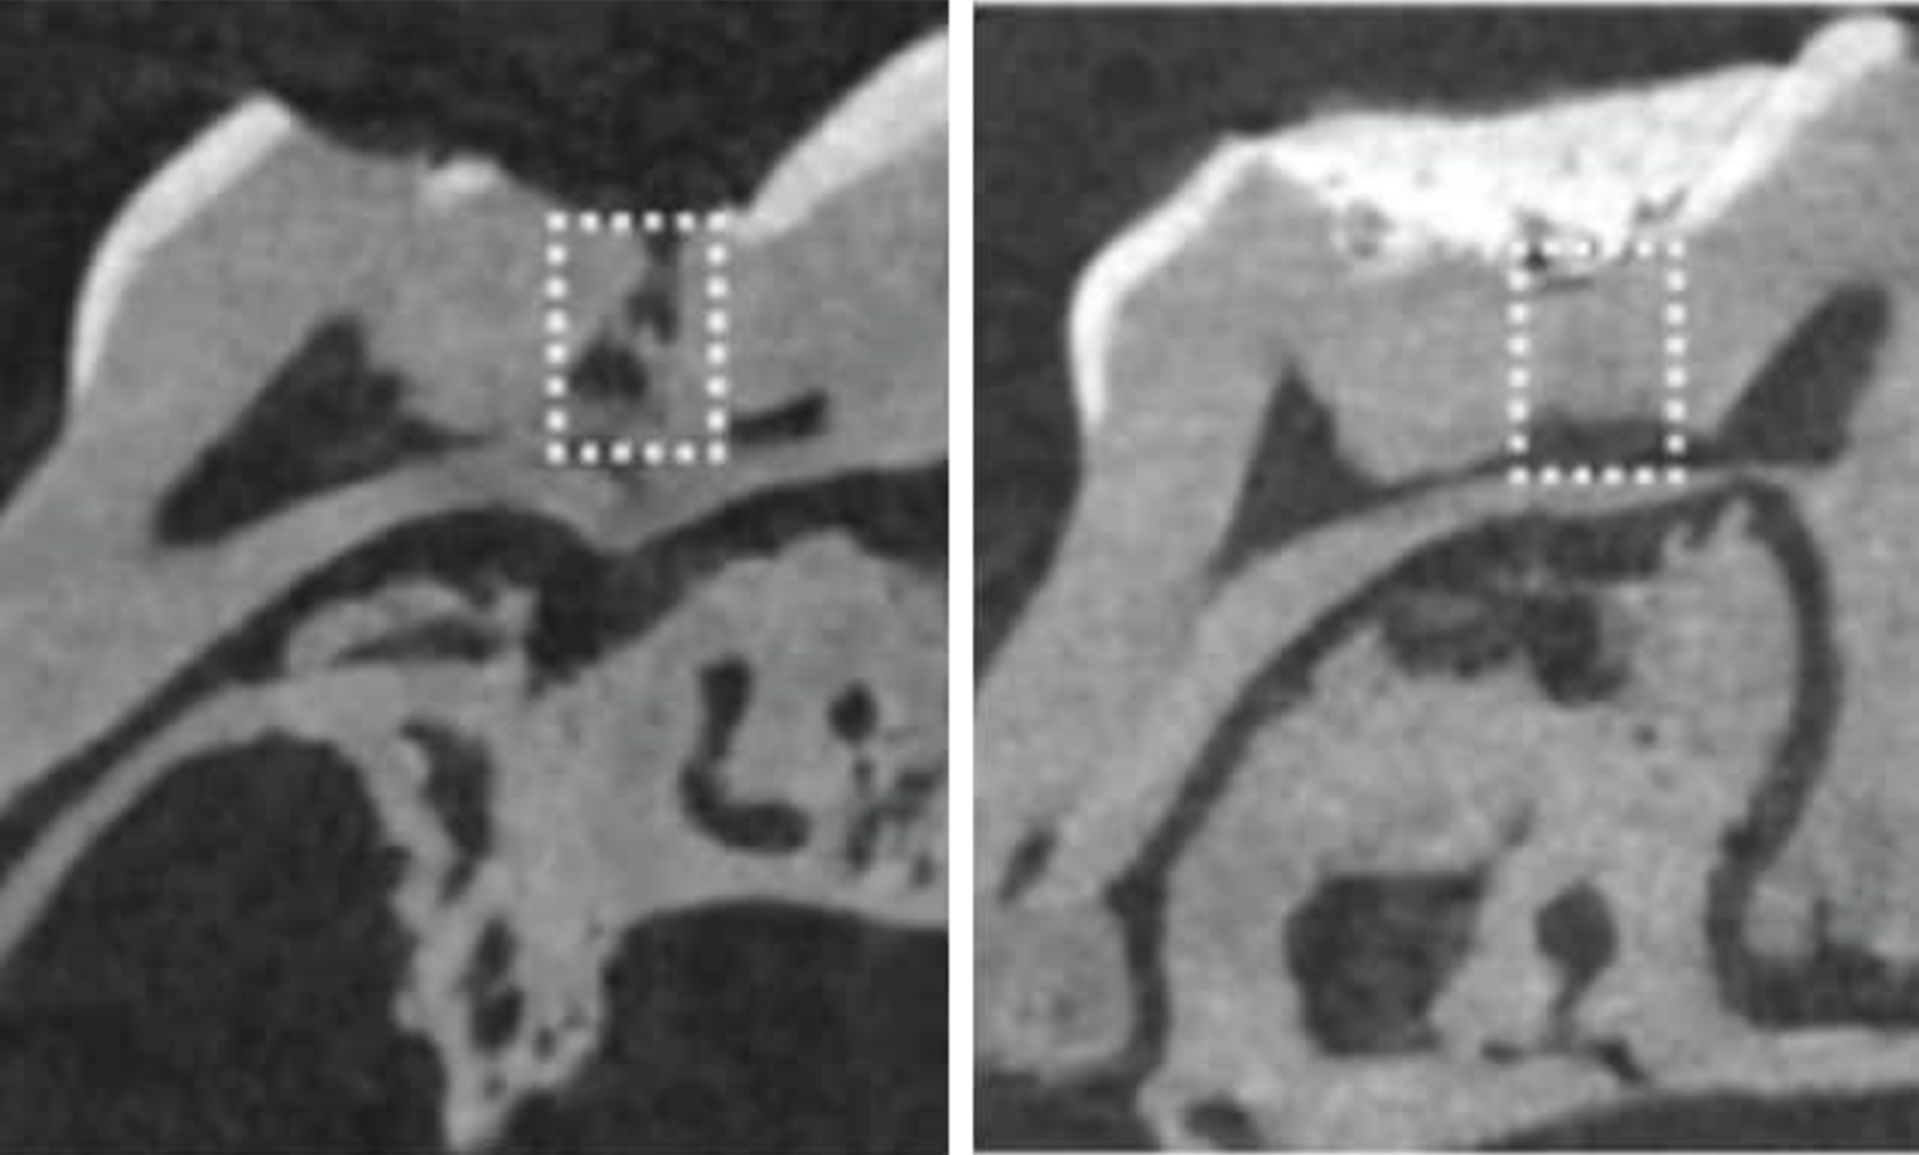

Foto: KING'S COLLEGE

Foto: KING'S COLLEGE

Celá liečebná metóda by mala vyzerať tak, že by sa biodegradovateľná „špongia“ namočila do liečiva a vložila do diery v zube. Tým by sa spustil rast zuboviny a celá diera by mohla byť zacelená už do šiestich týždňov. Keďže dané špongie by boli vyrobené z kolagénu, časom by sa samy rozložili a ostal by len opravený zub.

Zatiaľ bola táto terapia odskúšaná len na chrupe myší. No keďže klinické testy ukázali, že liek tideglusib je pre ľudí bezpečný, neostáva veľa prekážok, aby sa nový spôsob opravy zubov nevyskúšal aj na pacientoch. Vedci však neuviedli konkrétny časový horizont. Dovtedy ostanú klasické plomby najpoužívanejším spôsobom opravy zubov poškodených zubným kazom.